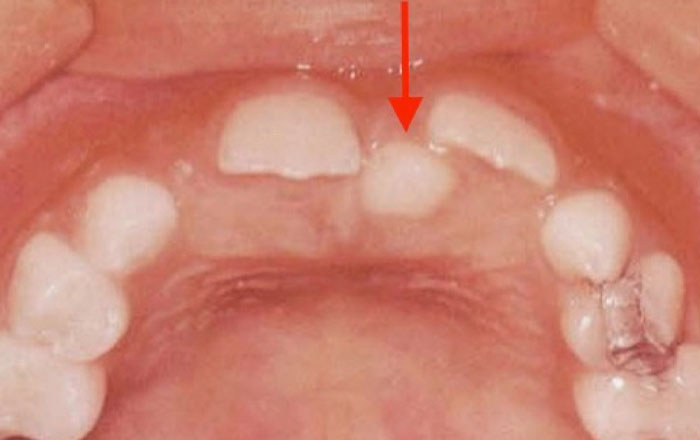

子どもの歯が、通常の本数より多く生えた歯を「過剰歯」と言います。

過剰歯が生えやすい場所は、

1)上の前歯と前歯の間

2)前歯から数えて4・5番目の小臼歯と言われる部分

に生えやすいと言われています。